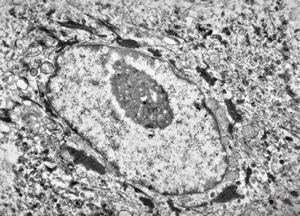

M, 11y. | mycosis fungoides v.s. - cerebriform nucleus of Sézary cell